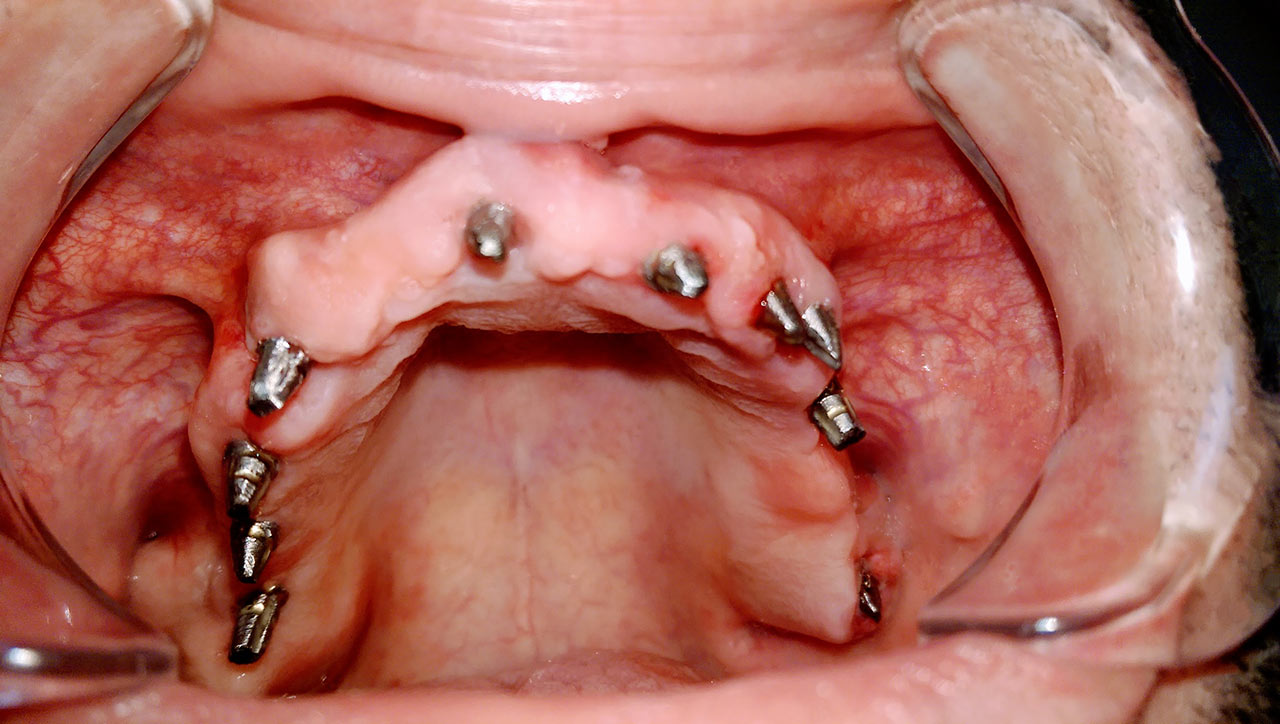

Teljes fogatlanság helyreállítása 2 nap alatt azonnal terhelhető svájci IHDE implantátumokkal és PMMA műanyag hidakkal. Intraorális szkennerrel vettünk lenyomatot az implantáció után, és erre a digitális mintára készítette el a fogtechnika a hidak digitális tervezését, majd faragta ki műanyagból. Ezt a gyors munkát az azonnal terhelhető implantátumok és a digitális lenyomat, tervezés segítségével tudtuk megcsinálni mindössze 2 nap alatt. Dr. Kelemen Péter és a Symbion Fogtechnika munkája.

Ismét egy teljes szájüregi rehabilitáció két lépésben. Először az alsó fogak lettek kihúzva és azonnal implantálva, híddal ellátva, majd később a felső. IHDE svájci azonnal terhelhető implantátumok és cirkónium hidak. Dr. Kelemen Péter és a Symbion Fogtechnika közös munkája.